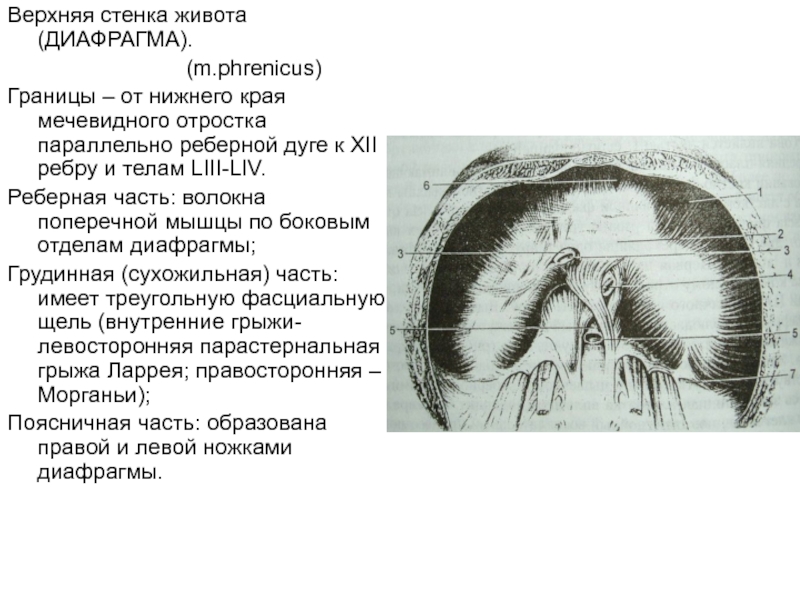

Анатомия диафрагмы и треугольника Бохдалека